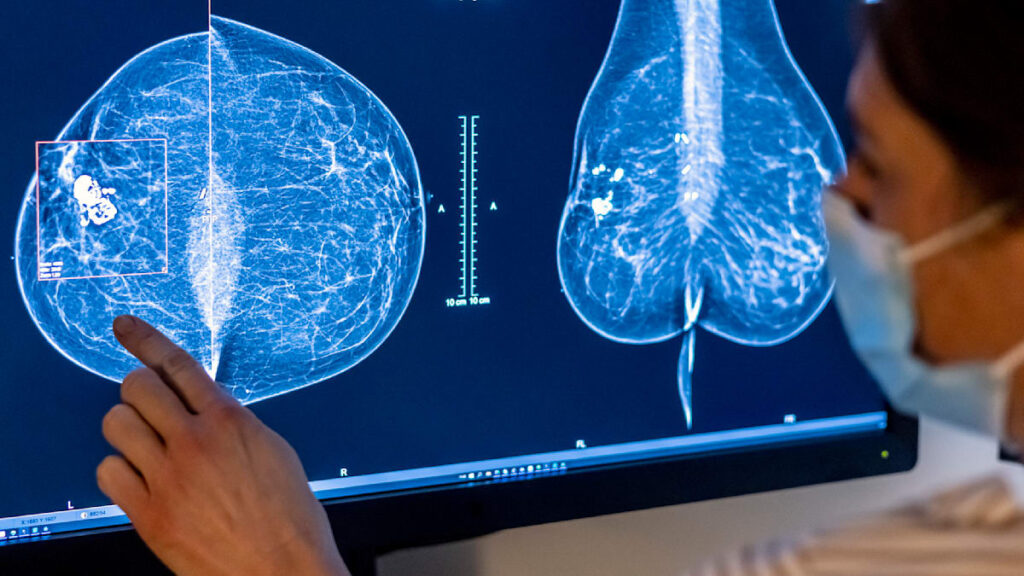

Ein Medizin-Skandal erschüttert Spanien. Frauen, die sich zur Brustkrebs-Vorsorge einer Mammografie unterzogen haben, erfuhren teils erst nach Monaten von nötigen Untersuchungen. In mehreren Fällen wurden Tumore zu spät erkannt.

Mit einer Mammografie lassen sich Tumore oft finden, bevor sie sich ertasten lassen – und je früher ein Karzinom erkannt wird, desto besser sind die Heilungschancen. Fortgeschrittener Brustkrebs, bei dem es bereits Metastasen gibt, ist hingegen in der Regel nur noch schwer heilbar. Es gibt aber Therapien zur Überlebensverlängerung.

Betroffene Frauen beklagten, es seien teils Monate oder noch länger vergangen, bevor sie erfuhren, dass eine Folgeuntersuchung nötig wäre. In mehreren Fällen wurde der Tumor erst spät erkannt. Krankenkassen, Patientinnenorganisationen und Berufsverbände kritisierten, solche Verzögerungen könnten die Heilungschancen drastisch mindern.